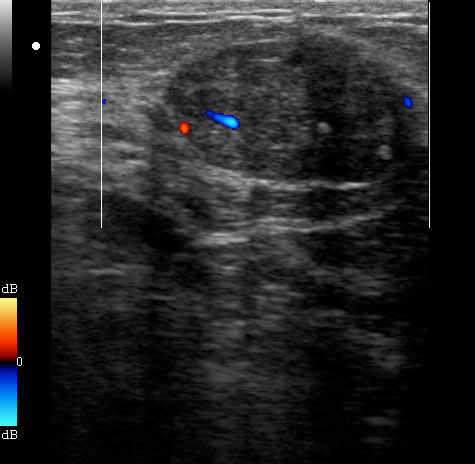

Узи молочных желез на авиамоторной - фото презентация